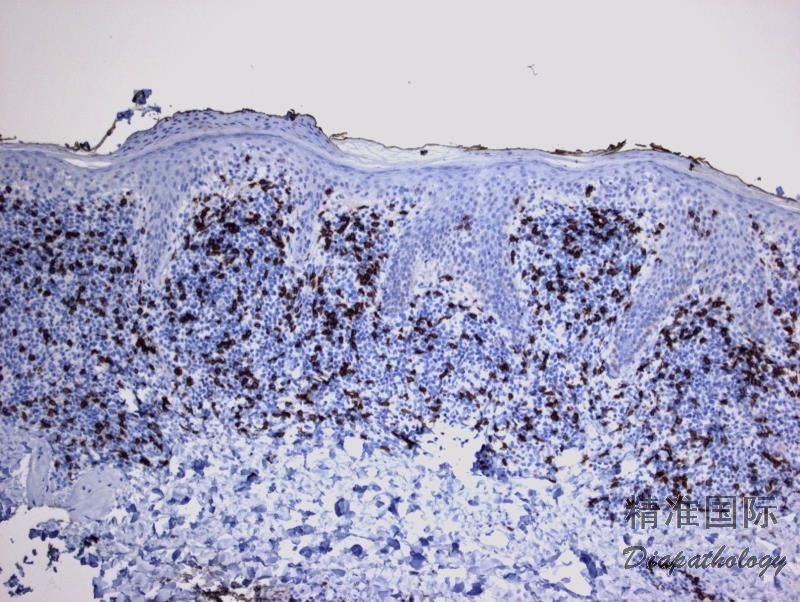

免疫表型:肿瘤细胞 CD3+、CD4+、βF1+、PD1+、CXCL13. CD30-、CD8-(散在+),常混合有 CD20+ B 细胞(有时量较多);BCL6+/-,CD10-;Ki67 5%(最高不超过 20%);EBER-

免疫组织化学染色:

肿瘤细胞 CD3+、CD4+、βF1+、PD1+、CD30-、CD8-(散在+),常混合有 CD20+ B 细胞(有时量较多)。